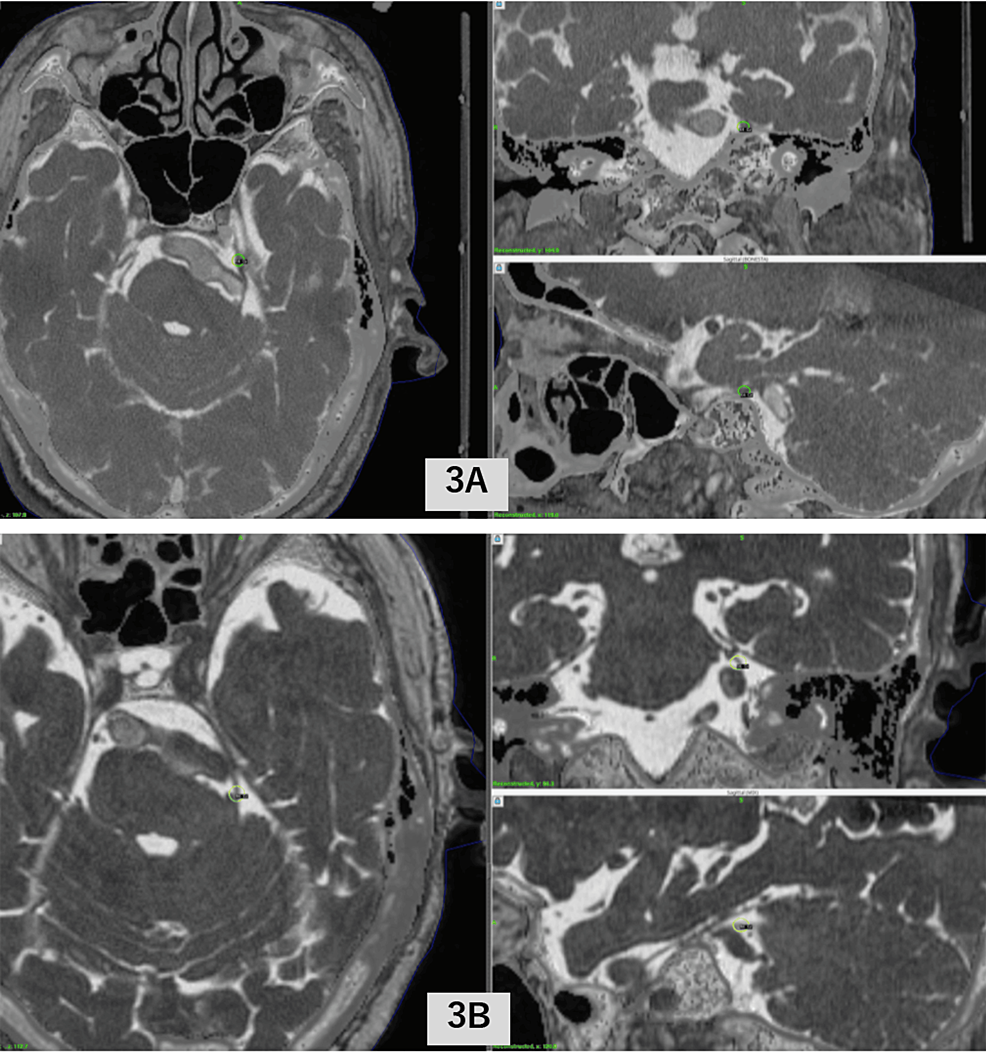

Stereotactic radiosurgery for trigeminal neuralgia secondary to tumor Stereotactic Radiosurgery For Trigeminal Neuralgia Stereotactic radiosurgery is an effective treatment option for trigeminal neuralgia (tn), with frameless stereotactic radiosurgery. Trigeminal neuralgia is a chronic pain condition of the trigeminal nerve affecting 12 per 100,000 people. Trigeminal neuralgia is a chronic pain condition of the trigeminal nerve affecting 12 per 100,000 people. Radiosurgery was first attempted for trigeminal neuralgia in the early 1970s by lars. Stereotactic Radiosurgery For Trigeminal Neuralgia.

Stereotactic radiosurgery for trigeminal pain secondary to recurrent Stereotactic Radiosurgery For Trigeminal Neuralgia The aims of this systematic review are to provide an objective summary of the published literature specific to the treatment of classical trigeminal neuralgia with stereotactic radiosurgery (rs) and to develop consensus guideline recommendations for the use of rs, as endorsed by the international society of stereotactic radiosurgery. Trigeminal neuralgia is a chronic pain condition of the trigeminal nerve affecting. Stereotactic Radiosurgery For Trigeminal Neuralgia.

Stereotactic Radiosurgery for Trigeminal Neuralgia Caused by Stereotactic Radiosurgery For Trigeminal Neuralgia Trigeminal neuralgia is a chronic pain condition of the trigeminal nerve affecting 12 per 100,000 people. Trigeminal neuralgia is a chronic pain condition of the trigeminal nerve affecting 12 per 100,000 people. Radiosurgery was first attempted for trigeminal neuralgia in the early 1970s by lars leksell, who used the stereotactic technology. Stereotactic radiosurgery is an effective treatment option for trigeminal. Stereotactic Radiosurgery For Trigeminal Neuralgia.